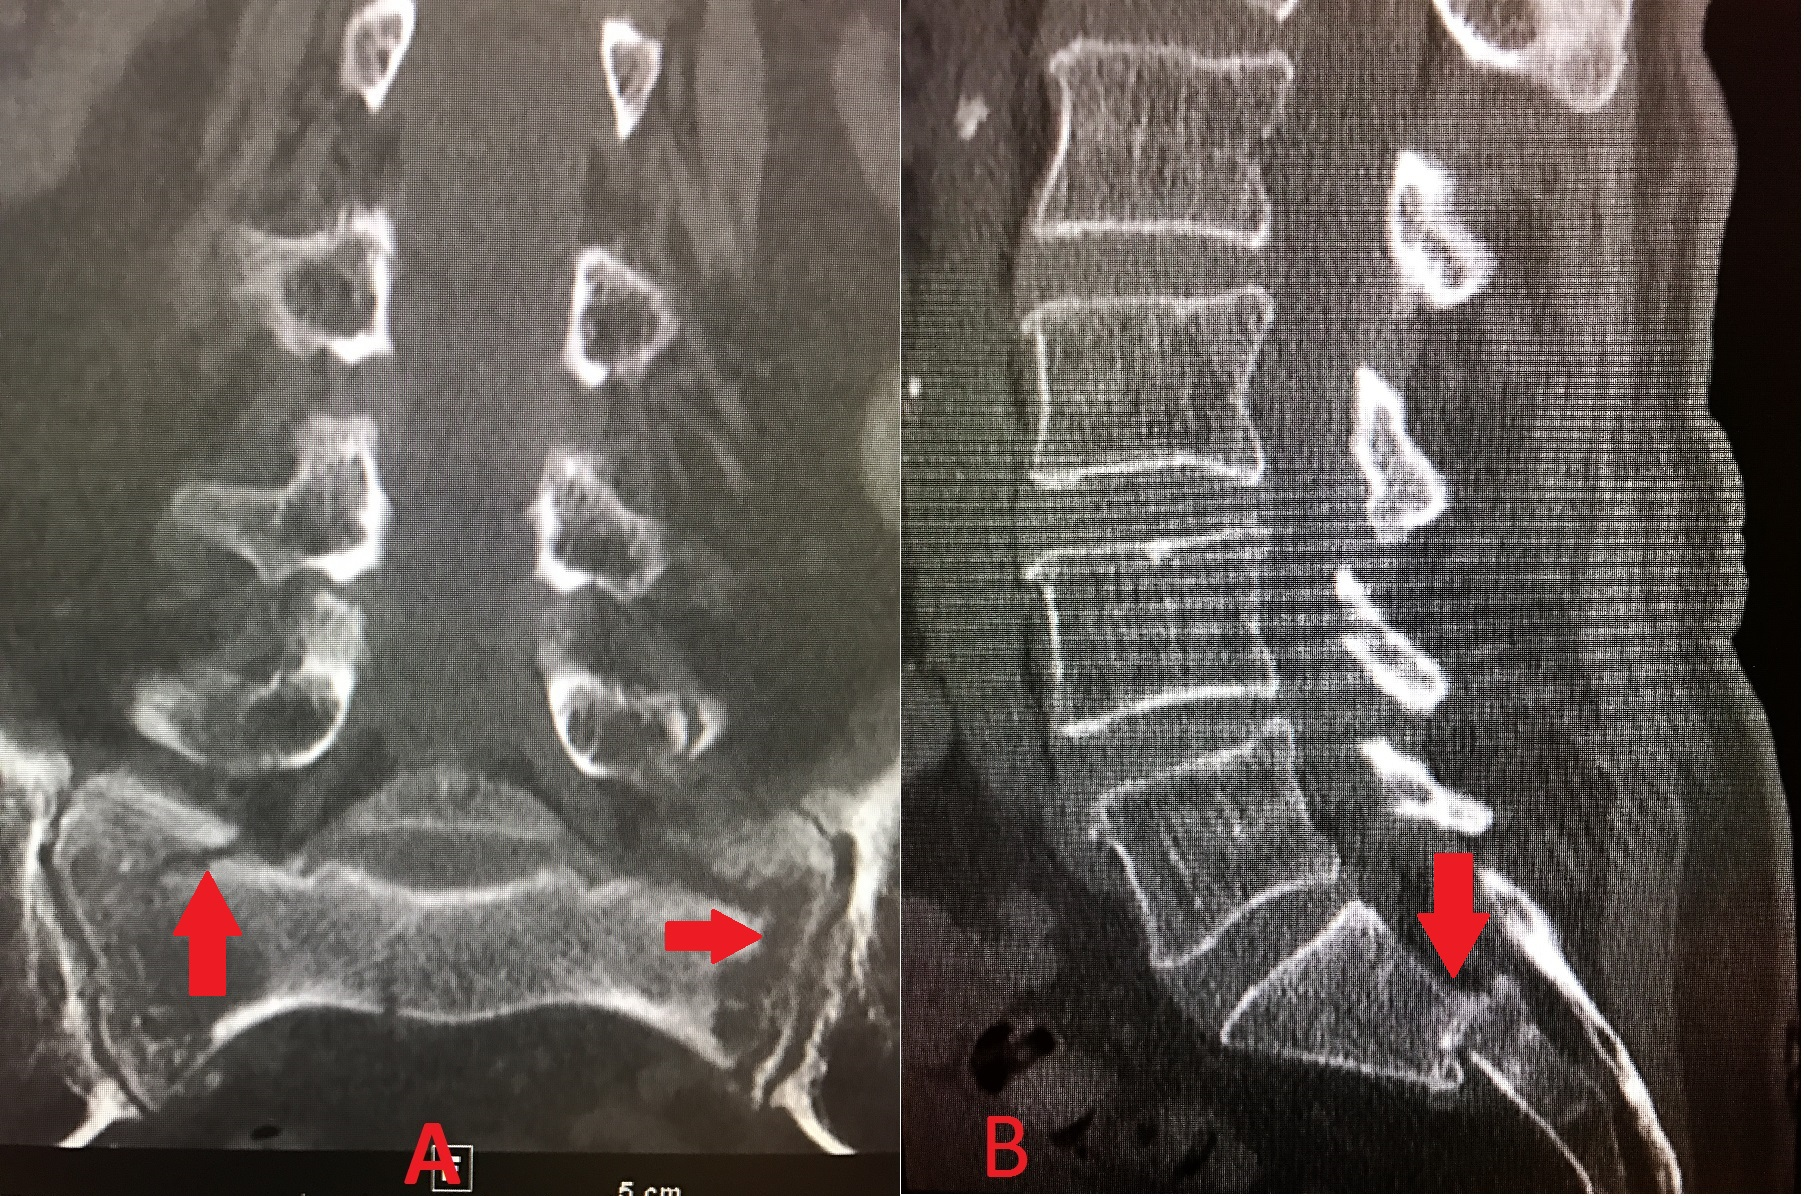

Cureus Bilateral Bertolotti's Syndrome A Case Report of an Does Ct Lumbar Spine Include Sacrum Ct lumbar spine without contrast is a valuable diagnostic imaging technique used to examine the lower back area, specifically the. A ct scan of the spine may be performed to assess the spine for a herniated disk, tumors and other lesions, the extent of injuries, structural. Computed tomography (ct) of the spine has remained an important tool in the investigation. Does Ct Lumbar Spine Include Sacrum.

Cureus Combined Sacroplasty and Iliosacral Fixation Using Triangular Does Ct Lumbar Spine Include Sacrum Computed tomography (ct) of the spine has remained an important tool in the investigation of spinal pathology. Ct lumbar spine without contrast is a valuable diagnostic imaging technique used to examine the lower back area, specifically the. A ct scan of the spine may be performed to assess the spine for a herniated disk, tumors and other lesions, the extent. Does Ct Lumbar Spine Include Sacrum.